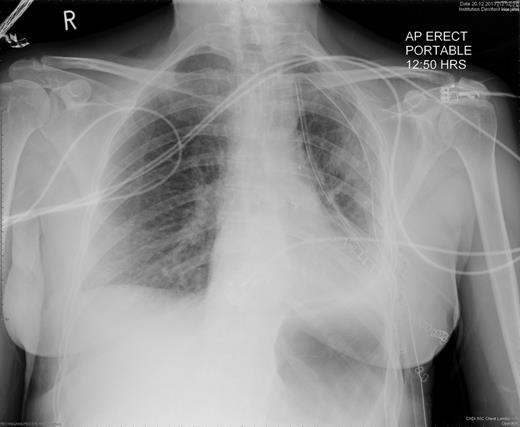

A 57-year-old woman with a left upper lobe mass was referred to our institution for lung resection. Preoperative computed tomography (CT) and positron emission tomography were consistent with lung cancer. Pulmonary function tests revealed a forced expiratory volume in 1 s of 1.64 l (64% predicted), forced vital capacity of 3.1 l (104% predicted) and TLCO of 97% predicted. The patient underwent an uncomplicated left upper lobectomy through open thoracotomy. The fissures were complete, and the inferior pulmonary ligament was mobilized in part. A systematic nodal dissection was performed. She was extubated immediately after surgery and was transferred to the ward as per routine practice. Post-operative chest radiograph revealed satisfactory expansion of the left lower lobe (Fig. 1). On the first operative day, the patient remained haemodynamically stable, without systemic upset, but developed atrial fibrillation with tachycardia. Chest X-ray demonstrated complete opacification of the left hemithorax with normal position of the left hemidiaphragm (Fig. 2). Urgent rigid bronchoscopy revealed narrowed left lower lobe bronchial orifice and the bronchoscope could not pass through. The left upper lobe bronchial stump was intact. Immediate exploratory thoracotomy was performed. At surgery, the left lower lobe had undergone a 180° anti-clockwise torsion at its brochovascular pedicle. The lung parenchyma was very fragile and haemorrhagic, compatible with early venous infarction, hard with a dark reddish surface. Torsion of the lower lobe was corrected and lower lobe was sutured to pericardium, in order to further investigate the anatomy, and determine whether completion pneumonectomy could be avoided. Her AF resolved with restitution of the lobe. A minitracheostomy was inserted prophylactically. However, over the course of the first few post-operative hours, the patient became progressively more hypoxic and tachypnoeic. CT was performed, demonstrating acute obstruction with possible angulation of main pulmonary artery and complete obstruction of left main bronchus (Fig. 3), reported as demonstrating recurrent torsion. The patient returned to theatre for a third time, and at throacotomy, the lobe was found to be in its normal position, but there was now further evidence of infarction, and completion pnuemonectomy was performed. Histological examination confirmed haemorrhagic congestion throughout the left lower lobe parenchyma. Post-operative course was uneventful and patient was discharged home on Day 7.

Chest radiography immediately after left upper lobectomy demonstrates good lower lobe expansion.